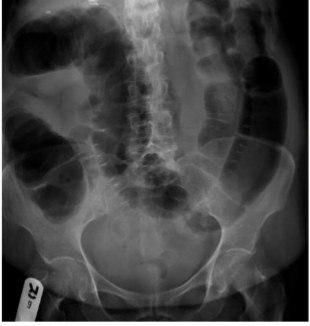

What is this and what type of scan

chronic constipation, abx